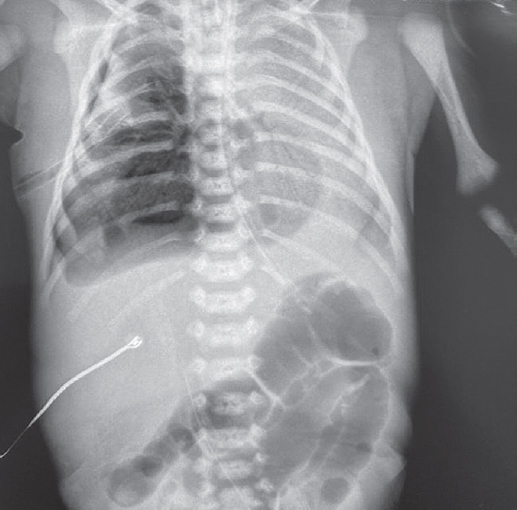

В статье представлен случай успешного лечения острого респираторного дистресс-синдрома у доношенного новорожденного, осложнившегося баротравмой легких, с применением монобронхиального введения экзогенного сурфактанта под рентгенологическим контролем. С целью оценки течения заболевания и эффективности лечения проведен ретроспективный анализ медицинской документации. С первых минут жизни у ребенка отмечались дыхательные расстройства, что стало основанием для проведения неинвазивной искусственной вентиляции легких. В динамике выявлено прогрессирование гиперкапнии и гипоксемии, в связи с чем была выполнена интубация трахеи и начата конвекциональная искусственная вентиляция легких с FiO2 = 1,0. Ключевой элемент терапии, позволивший достичь стабилизации состояния и регрессирования нарушений газообмена с полным выздоровлением пациента, — монобронхиальное введение экзогенного сурфактанта.